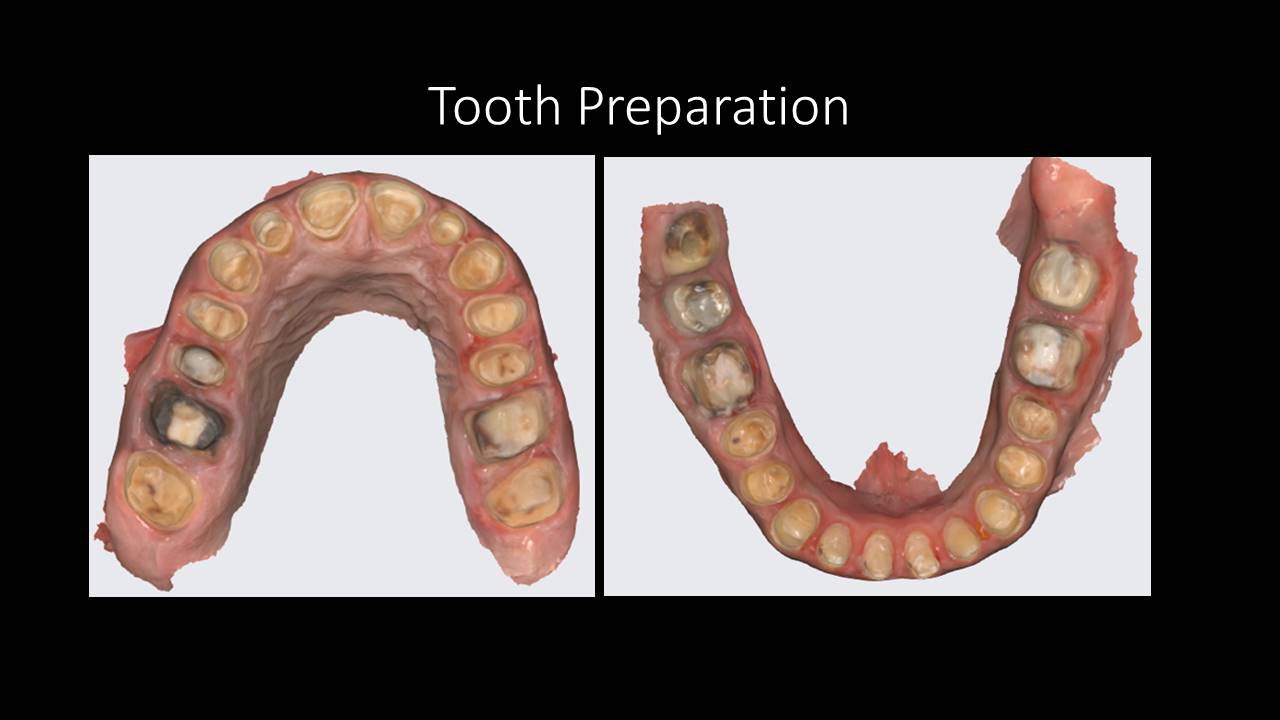

A complete reconstruction typically involves a combination of:

- Ceramic crowns, bridges, veneers & onlays

- Bite re-establishment & vertical dimension restoration

Each treatment plan is uniquely tailored based on the patient’s bite pattern, bone support, jaw movements, and aesthetic expectations.